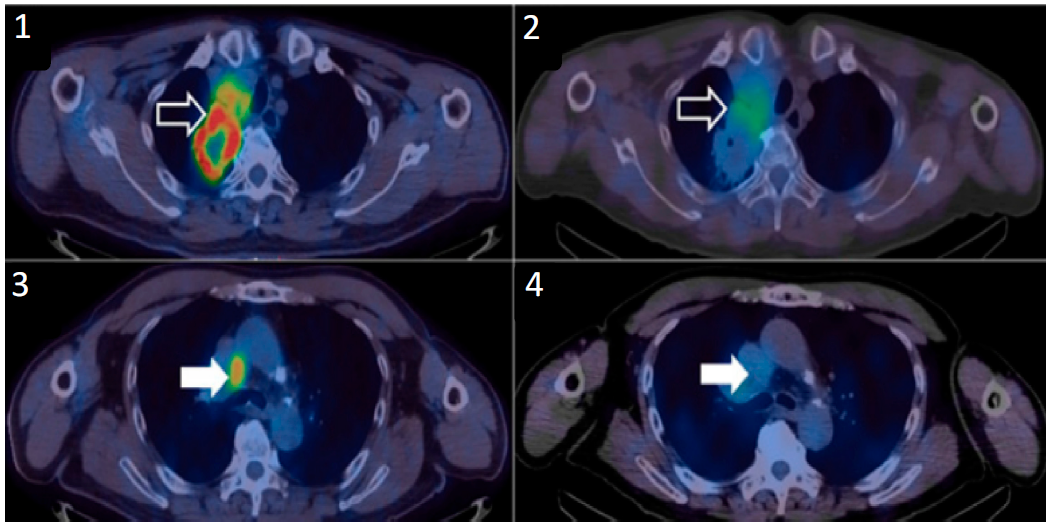

圖四、99mTc-NM-01在(NSCLC)患者中的成像數據?;颊叩挠疑戏稳~腫瘤顯示了高[18F]FDG攝?。?);以及高99mTc-NM-01攝?。?);縱隔淋巴結顯示了高[18F]FDG攝?。?);以及低99mTc-NM-01攝?。?);表明 PD-L1 在同一患者的原發(fā)腫瘤部位和遠處疾病部位之間存在異質(zhì)性表達6。

99mTc-NM-01此前已在中國完成了早期一期臨床試驗(NCT02978196)(圖四),評估了99mTc標記的抗PD-L1納米抗體在非小細胞肺癌(NSCLC)中的安全性、劑量學(xué)和成像效果,與金標準——組織活檢相比,99mTc-NM-01成像結果具有良好的一致性,有可靠且非侵入性評估 PD-L1 表達的潛力。目前,該影像劑正在英國進(jìn)行新一輪的臨床試驗(NCT04992715和NCT04436406),旨在評估99mTc-NM-01的診斷性能。